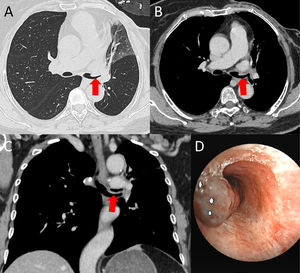

A 70-year-old woman with a history of breast cancer presented with a 6-month history of hemoptysis and cough, with clinical worsening over the preceding week. Chest computed tomography (CT) (Fig. 1A–C) demonstrated intraluminal masses within the left main bronchus and left upper lobe bronchus, resulting in airway obstruction and associated atelectasis. Flexible bronchoscopy (Fig. 1D) revealed a smooth, purplish-red mass causing severe stenosis of the left main bronchus and complete occlusion of the left upper lobe bronchus. Both lesions were completely removed using an electrosurgical snare.

Unenhanced chest CT (A) revealed intraluminal neoplastic masses in the left main bronchus and left upper lobe bronchus (arrow), causing obstruction and atelectasis. Enhanced venous-phase images (B, C) demonstrated progressive and marked contrast enhancement of the masses (arrows). Bronchoscopy (D) revealed the presence of a smooth, purplish-red neoplasm inside the left main bronchus.